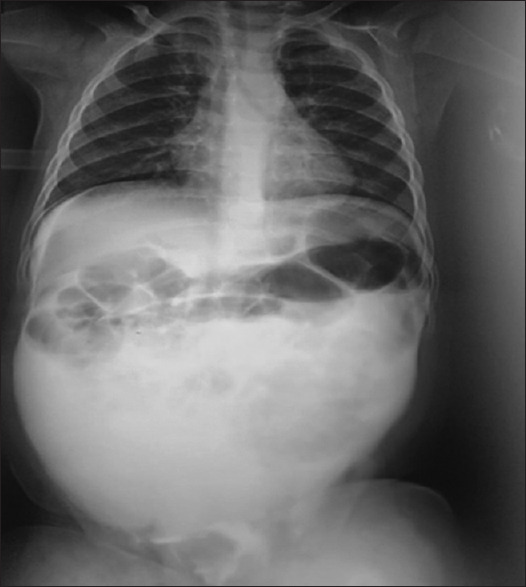

Abstract: Iatrogenic bladder rupture in children during a retrograde cystourethrography is very uncommon. We present a case of iatrogenic intraperitoneal bladder rupture in a 9-month child during the retrograde cystourethrography performed by a radiologist. The child presented in a paediatric emergency after 6 h with an acute abdomen indicating urinary peritonitis. An urgent laparotomy was performed and the perforation was repaired in two layers. The follow-up was unremarkable. This report emphasises the importance of respecting the criteria of the proper retrograde cystourethrography imaging procedure.